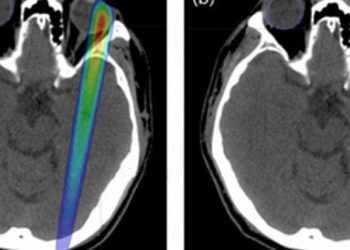

A new, international cancer trial using a combination of the drugs Ipilimumab and Nivolumab to treat people with advanced melanoma is showing insane results.